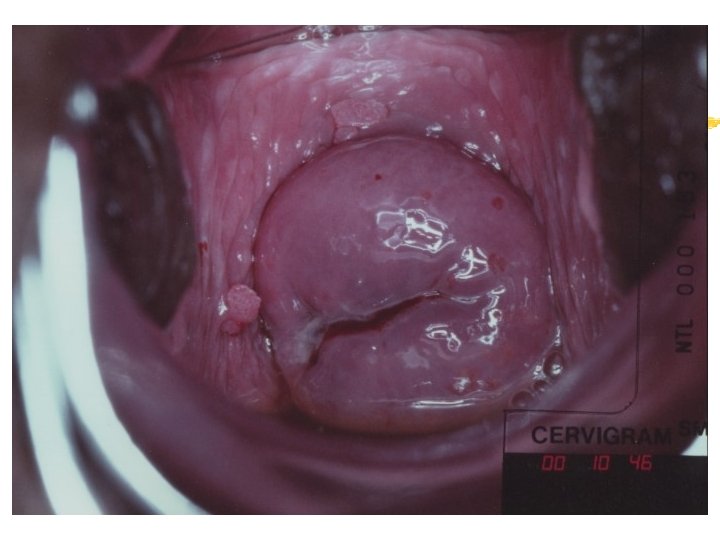

HPV infection Condyloma Accuminata Exophytic Frond like surface Lesion may be single or multiple Located within or outside the transformation zone

Cervicography: This is NOT Colposcopy High-quality colposcopic-type photography of the cervix Cervicoscope - Hand-held camera with a macrolens and a ring-flash Cervicogram - 35 -mm photo slide is taken Principles Recognition of lesions by means suitable magnification and illumination Fix up the problems of colposcopy 1. a less expensive form 2. noninvasive method 3. do not require expert skill

Procedures of cervicography A) Taking a 35 -mm cervicogram (1) Insert speculum and open as wide as possible … expose an entire cervix and upper vagina (2) Apply first application of 5% acetic acid by dabbing … cleanse the cervix of blood and mucus (3) View the cervix through the cervicoscope … allows time to begin taking epithelial change (4) Apply second application of acetic acid. (5) Take two cervicogram pictures B) Developing the images C) Interpreting a magnified image that was projected on the screen (1) Negative if no definitive lesions are visible (2) Atypical if there was evidence of acetowhite lesion of doubtful significance (3) Positive if there was evidence of a minor or major-grade lesion or cancer